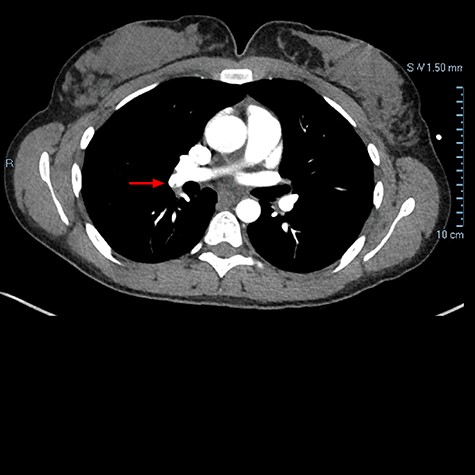

One week later, patient presented to ED with dyspnea on exertion and chest pain. Chest CTA demonstrated filling defect within the right lower lobar pulmonary arterial vasculature consistent with pulmonary embolus (Fig. 2). Patient was discharged with plan to follow up with vascular surgery, which continued course of apixaban as previously prescribed.

Chest CTA demonstrating filling defect within the right lower lobar pulmonary arterial vasculature consistent with pulmonary embolus as indicated by the red arrow.